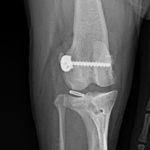

前十字靭帯部分断裂に対するLSS(ラテラルスーチャー法)

小型犬の前十字靭帯部分断裂にラテラルスーチャー法(以下LSS)を実施した。以前、膝蓋骨内方脱臼により大腿骨滑車造溝術、脛骨粗面移行術を行っている。今回、後肢に違和感があるとのことで早急に来院された。幸い完全断裂ではなく部分断裂のようである。大腿骨遠位にチタン製スパイクワッシャー とスクリューによりアンカーを作成、脛骨近位にボーンホールを形成し人工靭帯で締結した。小型犬では症状、年齢、ライフスタイルなどに合わせてLSSによる膝関節安定化術も治療オプションの一つである。